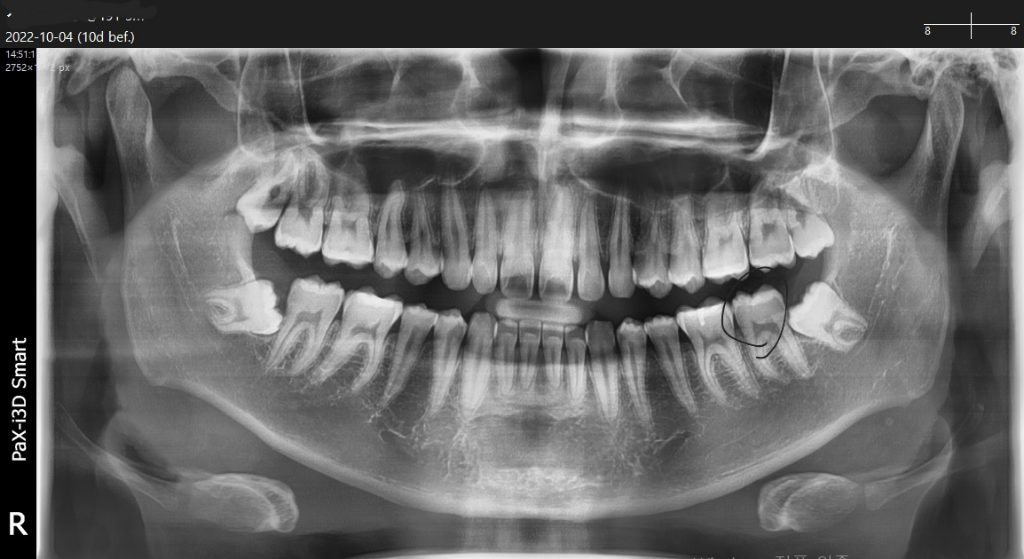

서면 유☆☆☆병원에서 문제없다했는데 한번 봐주실수있나요?

치아 동그라미친부분 심한 크랙 의심할수있나요? 치과 가보니까 심한충치는없고(정지성우식은 많음) 크랙도 심해보이진 않는다던데 동그라미친부분만 세게씹으면 칼로 쑤신듯이 아픈통증이 짧게 느껴집니다. 찬거 뜨거운것먹어도 이상없고 21세남자라 딱히 풍치같다는 느낌은 안드는데.. 왜그럴까요? 사랑니때문에 시린걸수도있나요?

파노라마 사진만으로는 크랙의 여부를 확인하기 어렵습니다

크랙은 방사선 사진보다 치아 자체의 를 봐야 확인할수 있는 경우가 다 많아요